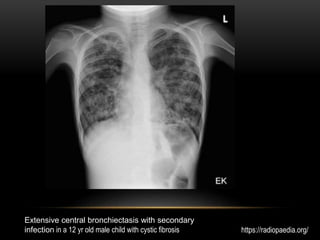

Extensive central bronchiectasis with secondary

infection in a 12 yr old male child with cystic fibrosis https://radiopaedia.org/